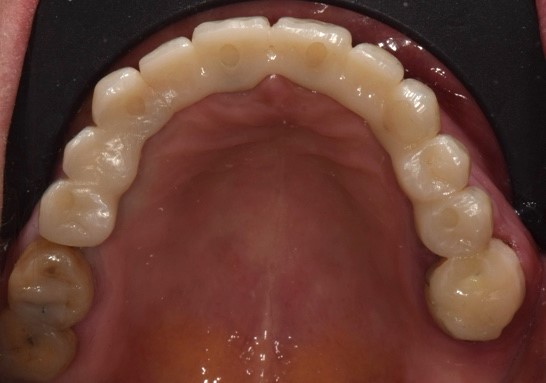

Situazione pre operatoria 1

Fig. 1(a)

Situazione pre operatoria 2

Fig. 1(b)

Una paziente di 65 anni si presentava presso la nostra clinica con ampie aree edentule (1° e 3° quadrante), un ponte con mobilità nel 2° quadrante e denti inferiori con scarso supporto parodontale ad eccezione del dente 46 (Fig. 1 a,b,c,d). Dopo un'accurata anamnesi ed esame della CBCT (CS9600®, Carestream Dental, Atlanta, USA) (Fig. 1d), si optava per estrarre le radici e i denti con una prognosi sfavorevole, lasciando 4 molari che credevamo potessero essere conservati (denti 16,17, 26 e 47) al fine di mantenere la dimensione verticale di occlusione (DVO) originale. Si progettava il posizionamento di 12 impianti: 6 impianti nella mascella e 6 nell'arcata inferiore.